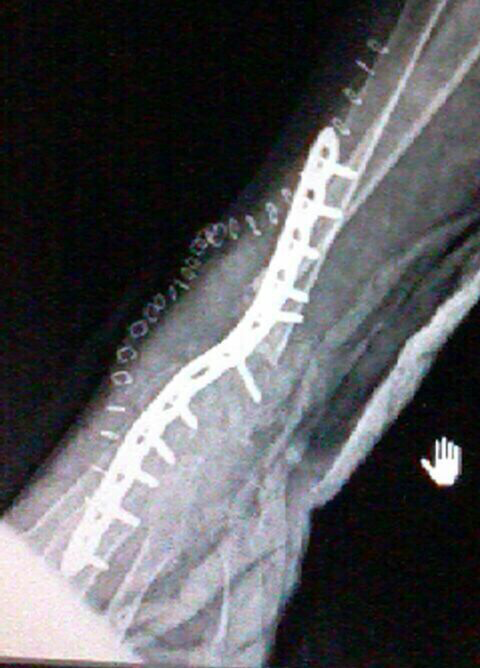

Wrist Deformity Correction